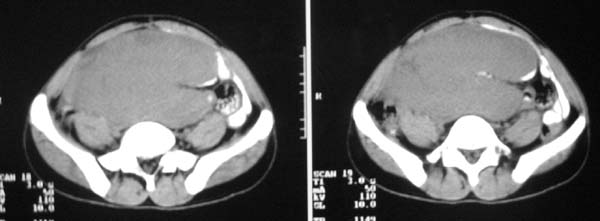

以下是引用guzhongliangddd在2007-9-27 23:21:00的发言:[br][br]与肠内高密度相同,病灶应该没有钙化,我认为首先考虑是间叶组织的良性肿瘤。建议楼主做后重建观察。中线区域大血管旁未见确切增大淋巴结。病灶对肠道只是推移关系。